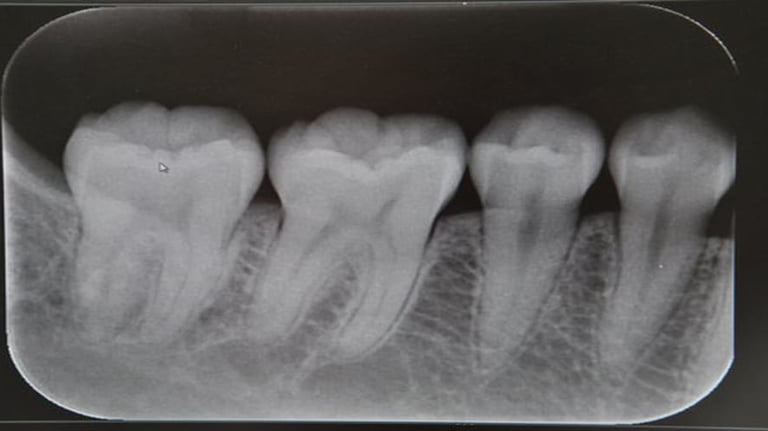

RADIOGRAFIA INTERPROXIMAL